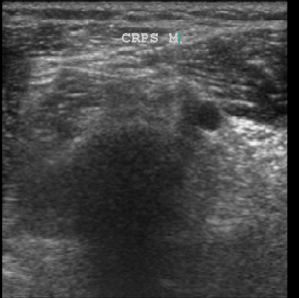

Most of our papers got rejected outright and there was not much we could do about it without some kind of objective evidence that could prove our hypotheses. This opportunity came in 2009. An ultrasonography (USG) machine company brought their machine for demonstration. So, I thought ‘let us see if the intrinsic muscle issues of CRPS can be visualized on USG’. I had two patients of CRPS in the clinic that day and what I saw on USG just blew me away. USG unequivocally showed in black and white what I had suspected all the time, that there was an intrinsic muscle abnormality in CRPS. This was obvious even to me without a formal training in muscle sonoanatomy.

Normal muscle on USG has clearly delineated muscle outlines and looks generally black with bright streaks of connective tissue framework that holds the muscle fibers in well-defined bundles. (fig 15) In stark contrast, the CRPS muscles in this patient looked like a sheet of barren white (fibrotic) tissue without any form or shape, with no discernible outlines. The bulk of muscle was also very much reduced in CRPS compared to normal muscles.

Figure 15 CRPS in a 26-yr-old after metacarpal fracture 18 months prior

Row 1- The ultrasound appearance of a normal muscle from the healthy limb. Note that the outlines of the muscles are clearly defined by shiny white borders and all the different muscles are identifiable and can be named. The muscles themselves have a dark background within a framework of supporting fibrous tissue which appears like shiny white streaks, and this is the typical sonographic signature of muscle. The second image shows her hand trying to make a fist, that she is unable to flex the fingers onto the palm or touch the tips of fingers to each other or thumb. Ultrasound of the CRPS limb in the 3rd image shows that there is no definition of muscle boundaries nor is there the normal contrast of black muscle in with white streaks of fibrous framework in between as compared to the ultrasound of the muscles of normal limb. In short there is a complete disruption of muscle structure.

2nd row- The first image shows that the patient has regained the ability to make a fist after 1month of USGDN of the forearm muscles. The patient opening the cap of a bottle 18 days after treatment which was impossible for her before USGDN at Ashirvad. Image C shows the return of normal structure to the muscles on ultrasound although there is still some predominance of fibrosis in the form of hyperechogenic fibrous streaks.

We found that these ultrasound changes of muscle structure disruption were consistently present in varying degrees in every patient that we examined thereafter. The USG changes of muscle abnormality appear as early as 15 days after the onset of CRPS and continue to be not just present but keep worsening till the muscle becomes completely fibrotic as indicated by the white-out appearance in all muscles affected by CRPS of medium or long duration. This was the picture that we saw in the first patient who had CRPS for 2 years. Subsequently we made it a part of our CRPS management protocol to routinely to document the muscle changes in every patient before USGDN, at 15 and 30 days and after the patient has recovered fully and correlate it with documentation of clinical findings.